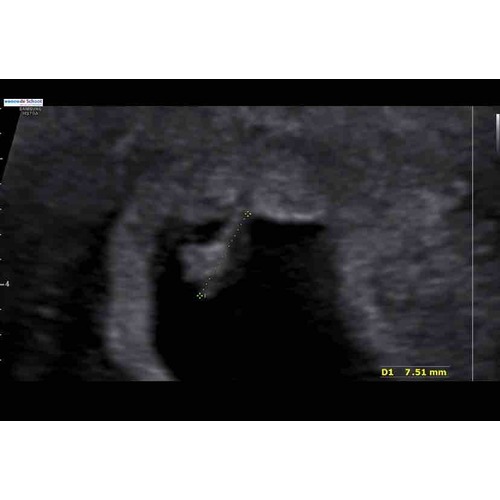

Hoi! Ja ik had een kloppend hartje! Eerst kon ze niks vinden en na 20 min eindelijk gevonden. Ik probeer nu maar zo te denken zo lang ik geen buikpijn/krampen of rood bloedverlies heb zal het wel goedkomen.. want ik maakte mezelf echt helemaal gek . Maar ik zie bij jou ook geen vruchtje zitten ? Hoe heeft ze het opgemeten bij jou?

Oh wat mooi zeg! Ik was binnen 10 minuten al buiten dus misschien is dat het verschil haha! Ja dat is inderdaad een goede gedachte moet ik ook maar eens doen! Nee dat klopt waarschijnlijk omdat ik te vroeg was en er enkel nu alleen een vruchtzakje is hopelijk is er morgen meer.. inwendig is het opgemeten.

Ze zeggen een gemiste miskraam omdat het vruchtzakje niet gegroeid is en het geen ronde vorm had. Ik weet niet wat ik moet geloven.. ze vragen nog geen eens naar mijn cyclus terwijl ik een cyclus van 36 dagen heb? Volgens mij ben ik gewoon nog te vroeg om iets te zien? Wat denken jullie?

Nou ja zeg ! Dit meen je niet ? Heb je een foto ? Hoever dacht je zelf ook alweer te zijn ? Vind dit erg raar allemaal ..